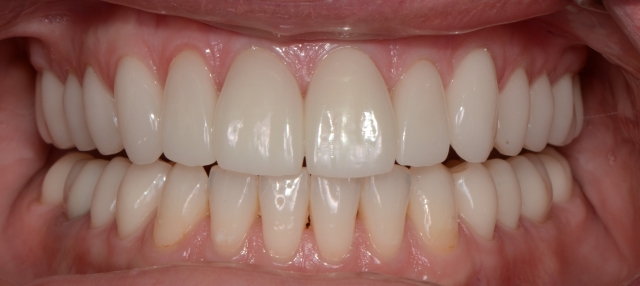

We finished the case using the designed-and-adjusted provisionals as our guide. Happy patient, happy dentist. Much more enjoyable trip to Africa.

The AEFSB protocol, slowing down to see more, and using a leaf gauge as an aid to locate seated condylar position — all things taught in the Occlusion in Clinical Practice workshop — meant the difference in the success of this significant restorative case. In many instances, it’s not the sophistication of our technology that makes us better dentists; it’s the knowledge to know when and why we need to slow down, to observe more, and to better understand what we are seeing that makes the difference. Application of straightforward protocol in diagnosis and planning is often the key.